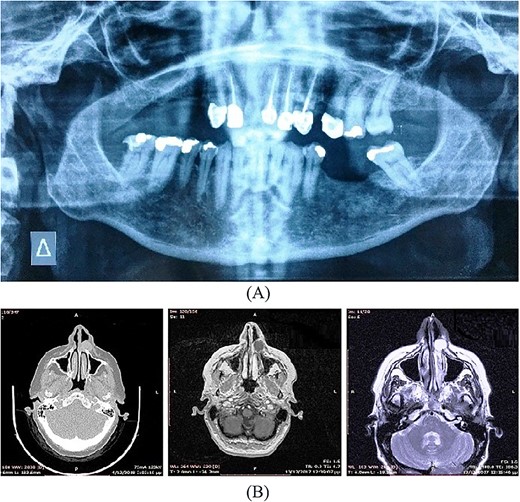

A 54-year-old-Caucasian female was referred to our department with a swelling of the left maxillary area (Fig. 1), actively inflaming. Antibiotics were prescribed, and after a week, the swelling persisted but was painless, roundish, fluctuant in palpation, sizing ~3 cm in diameter. The overlying mucosa was normal and mobile over the lesion. Clinical examination also revealed an extraoral asymmetry over the nasolabial sulcus because of the presence of this lesion causing obstruction of the left nostril. The patient presented with poor oral hygiene and the orthopantomogram revealed periodontal disease (Fig. 2a). CBCT imaging revealed a low density, ovoid, cystic soft tissue mass of 3.4 × 2.3 × 3 cm in close contact with the alar base. The maxilla near the lesion appeared concave, because of the cyst’s pressure, but without erosion (Fig. 2b). The patient was advised to undergo a contrast-enhanced computed tomography (CT) scan, but she did not wish to perform any other imaging study. The patient’s medical history was non-contributory.

A 57-year-old-Caucasian female patient was referred to our department, complaining of swelling of the left anterior maxillary area (Fig. 5a). The patient had been aware of the swelling for 20 months, but without any pain or tenderness. Physical examination revealed a 2-cm soft lump with normal overlying mucosa and mobile over the lesion (Fig. 5b). An extraoral asymmetry over the left nasolabial sulcus and obstruction of the left nostril was observed. The teeth, adjacent to the lesion, were endodontically treated. The cyst was not identified on the panoramic radiograph of the jaws (Fig. 6a). CT and magnetic resonance imaging (MRI) images showed an oval lesion with slight peripheral enhancement emanating from the lateral wall of the left nasal cavity (Fig. 6b). The lesion, measured 1.7 × 1.9 × 1.3 cm, was considered a simple cystic lesion. No erosion was evident on the underlying maxillary bone, despite its extension anteriorly to it.

Imaging includes an orthopantomogram to exclude other odontogenic lesions, and CT imaging to estimate the exact dimensions and the extension of the cyst to the neighboring structures of the nose. Imaging typically records a homogeneous, non-contrast enhancing cystic lesion anterior to the piriform opening. Remodeling of the underlying maxillary bone may be seen in larger cysts as well. Both present cases demonstrated in imaging well-defined cystic lesions in deep lateral nasal areas. On MRI, these cysts can appear as homogeneous intermediate intensity T1 signals and homogeneous high-intensity T2 signals. However, CT imaging is the preferred option in the pre-operative diagnosis of nasolabial cysts [11].